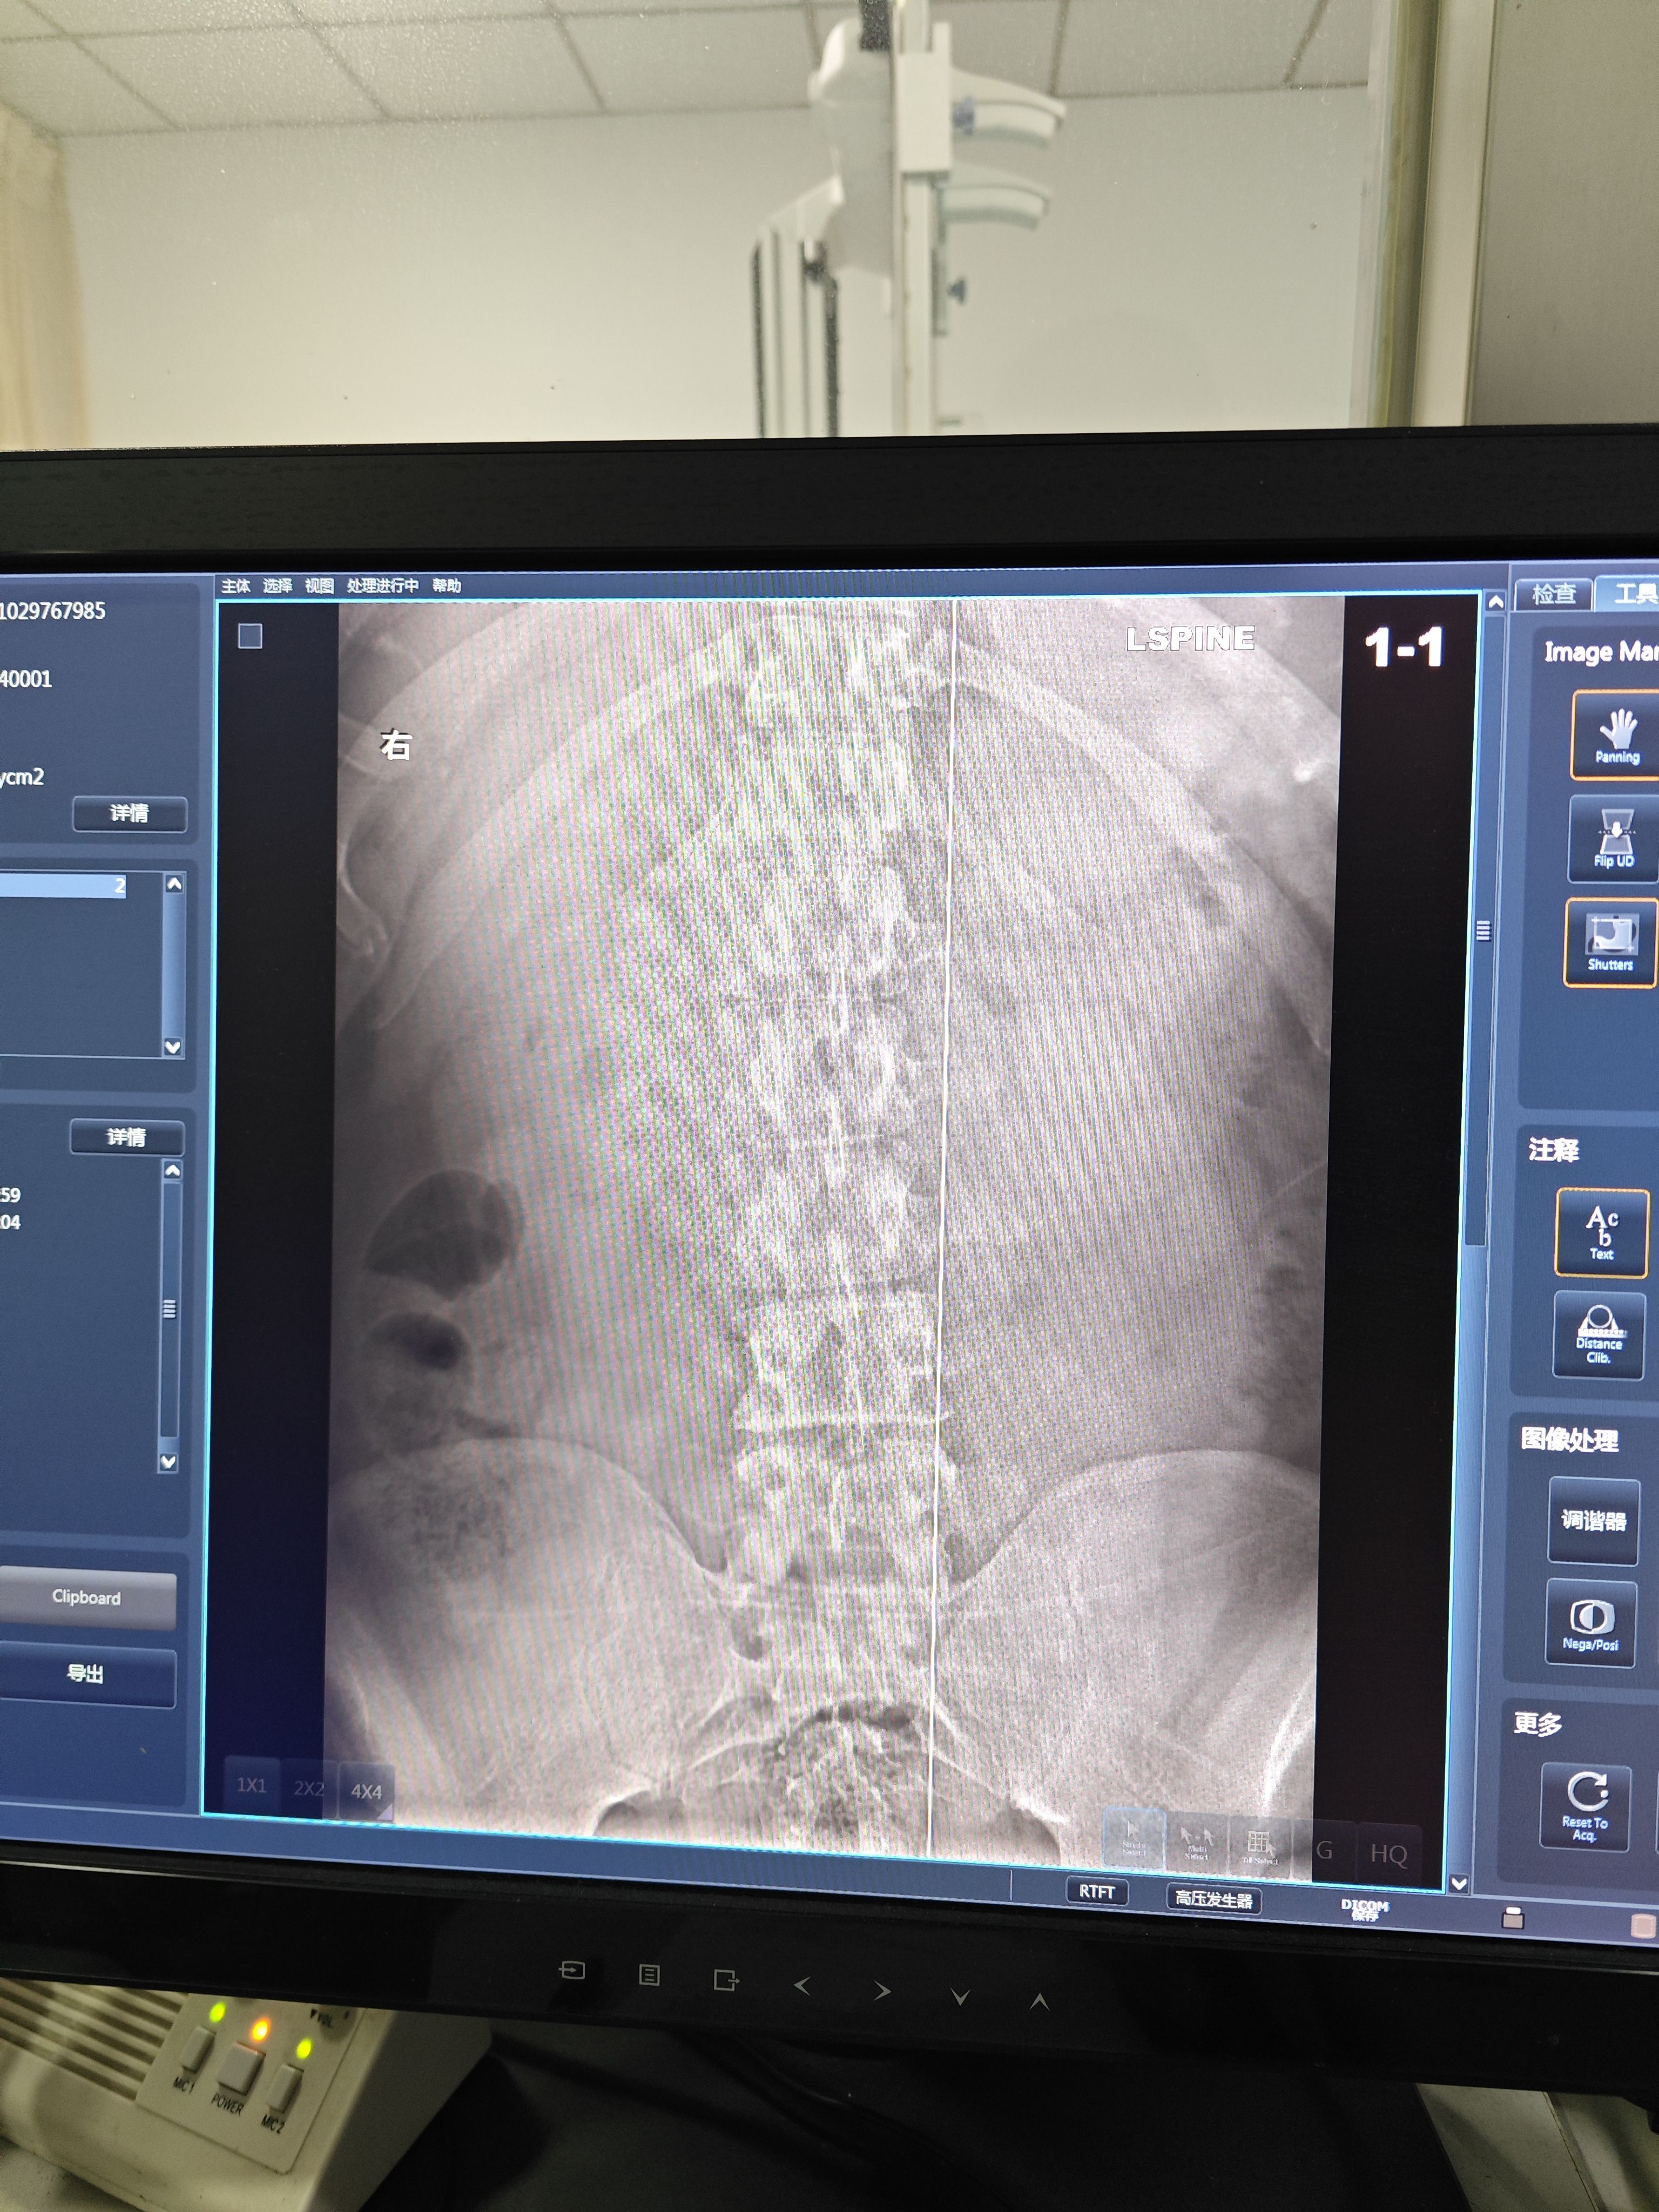

片子来力

收起 查看大图 向左旋转 向右旋转

有点点明显了已经,平常会不会下背痛,腰背累,晨僵之类的